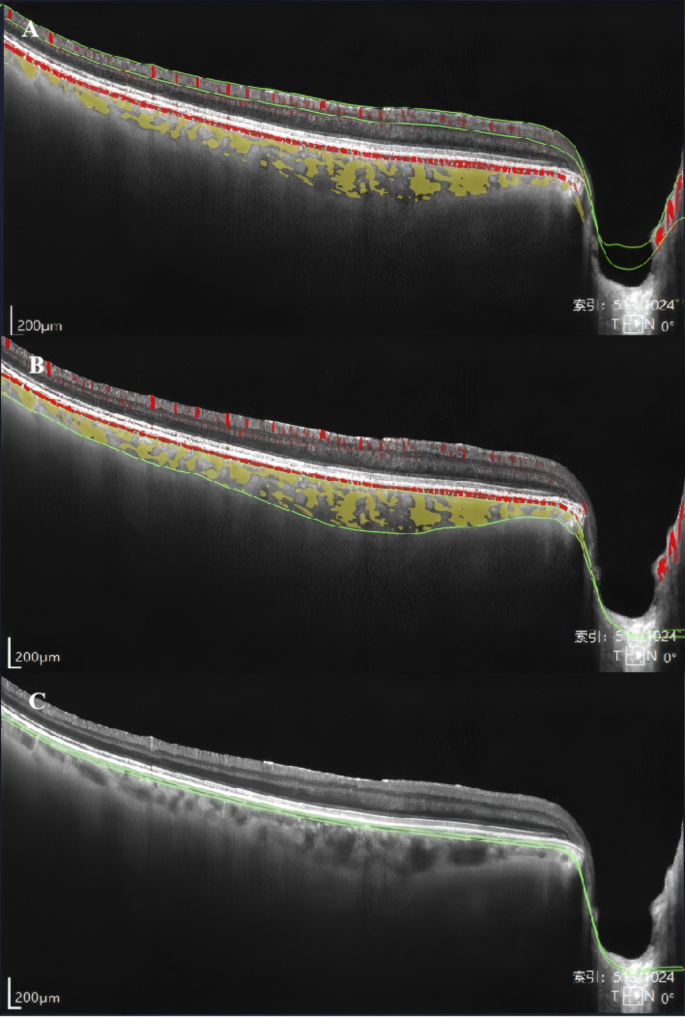

As shown in Fig. 1A, the retinal superficial vascular complex (SVC) was segmented from the internal limiting membrane (ILM) to the junction between the inner plexiform layer (IPL) and inner nuclear layer (INL). Retinal ganglion cell complex (GCC) thickness was defined as the sum of the retinal nerve fiber layer (RNFL), ganglion cell layer (GCL), and IPL, measured from the inner border of the RNFL (immediately beneath the ILM) to the IPL–INL junction. On B-scans, the visually appreciable extent approximately overlapped with the SVC16. The choroid was defined as the region between the BM and the CSI, and choroidal thickness (CT) as the perpendicular distance from the BM to the CSI. Using a built-in algorithm, the choriocapillaris slab was delineated from Bruch’s membrane (BM) to 29 μm below the BM, whereas the large and medium choroidal vessel layer (LMCVL) was defined from 29 μm below the BM to the CSI (Fig. 1B-C)16,17.

Segmentation of macular subregions, structure, and microvasculature. (A) Retinal SVC, defined as the area between the two green segmentation lines. (B) LMCVL, defined as the area between the two green segmentation lines. (C) Choriocapillaris, defined as the area between the two green segmentation lines.